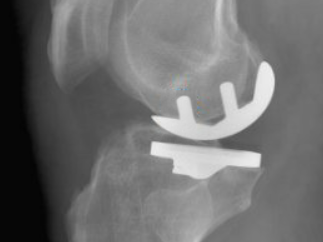

Qu'est-ce qu'une Prothèse uni-compartimentale de Genou?

Cette intervention consiste à remplacer une partie de l’articulation du genou, le compartiment fémoro-tibial interne ou externe, par des composants artificiels qui reproduisent l’anatomie initiale du genou. Le type d’implant doit être adapté à chaque cas particulier, en ce qui concerne sa forme, sa taille, la nature des matériaux entrant dans sa composition, son revêtement extérieur et la technique chirurgicale à employer.

Généralement, une prothèse de genou se divise en deux parties : un insert fémoral et une embase tibiale surmontée d’un polyéthylène. Les composants sont généralement fixés par du ciment.

Album photo